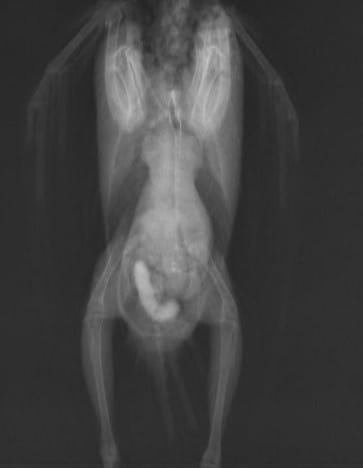

レントゲン検査では腸結石が確認されました。そのため、入院して治療していくことにしました。

このように結石が排出されました。